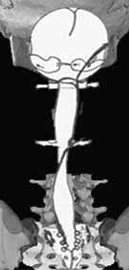

Category III Pattern Photo

Photo Cranial Sacral Pattern III